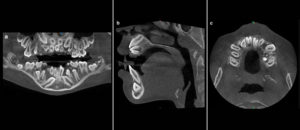

192 – Clasificación propuesta para los contactos interproximales de los molares primarios utilizando CBCT: Un estudio piloto

El «Área de contacto» es un término que se usa para denotar las alturas proximales del contorno de las superficies mesial y distal del diente.